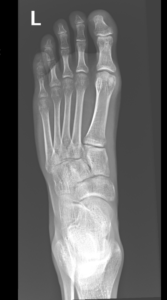

- Foot Fractures.